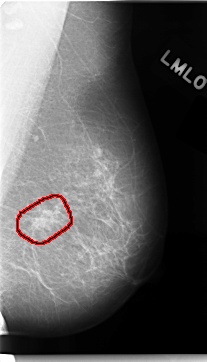

C_0047_1.LEFT_MLO

LEFT_MLO LINES 4696 PIXELS_PER_LINE 2680 BITS_PER_PIXEL 12 RESOLUTION 50 OVERLAY

FILE: C_0047_1.LEFT_MLO.OVERLAY

TOTAL_ABNORMALITIES 1

ABNORMALITY 1

LESION_TYPE MASS SHAPE IRREGULAR MARGINS SPICULATED

ASSESSMENT 5

SUBTLETY 5

PATHOLOGY MALIGNANT

TOTAL_OUTLINES 1

BOUNDARY